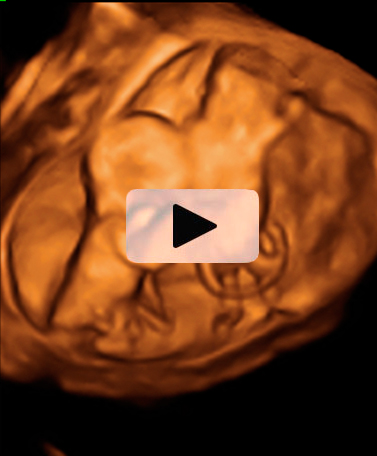

Ecografía Embarazo 2D y 3D Semana 12 - ANOMALÍAS CROMOSÓMICAS